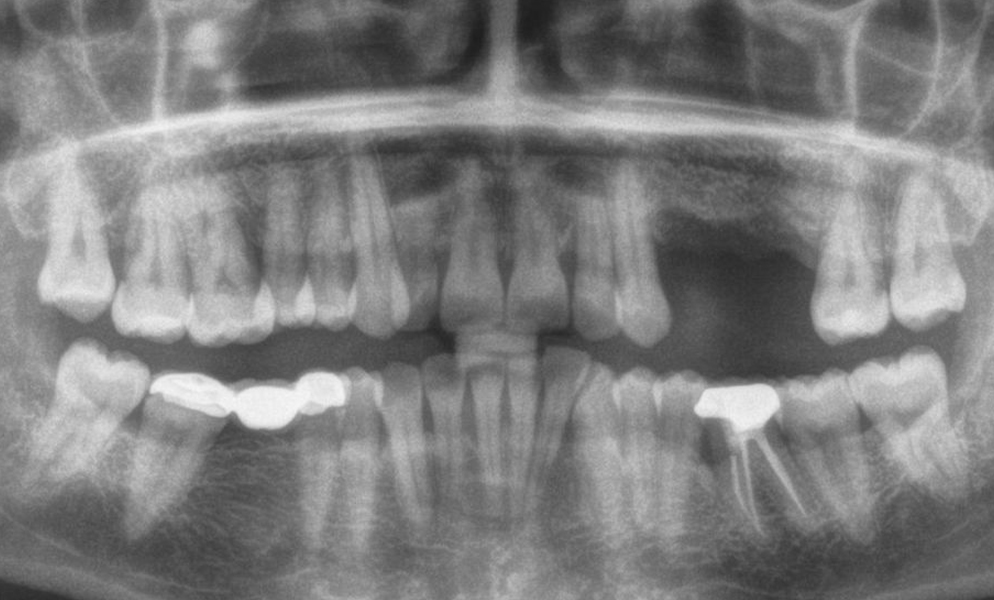

| Before | After |

![]() |

| Single posterior tooth missing space restored with a 4x6 mm short dental implant (Bicon, USA) to avoid sinus lift and bone graft procedures | |